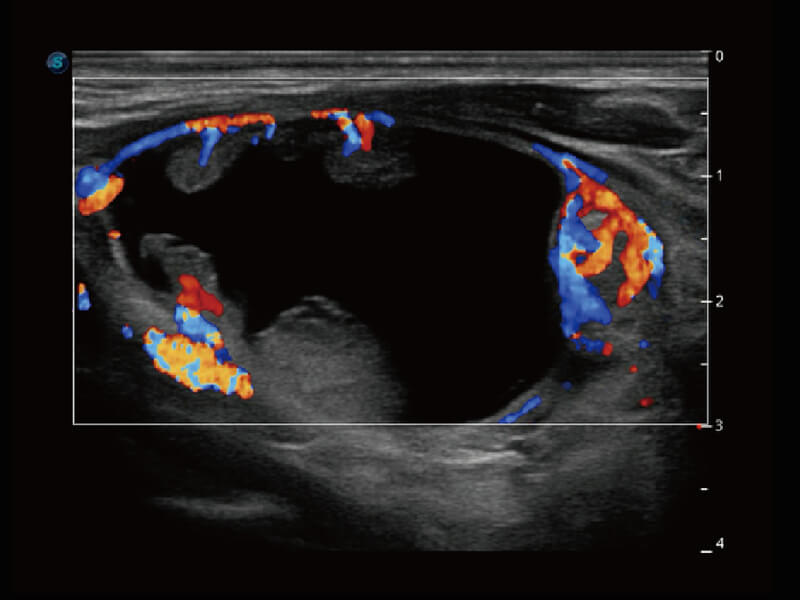

性能优异的硬件架构,极大提升超声系统的运行效率和数据处理能力。相比以往超声成像系统,Wis+平台为您带来极快的响应速度和成像帧频,提升检查流畅度。

S60探头工艺,从前端信号处理每一个环节采集无损声学数据,真实还原组织原貌,再现解剖细节。